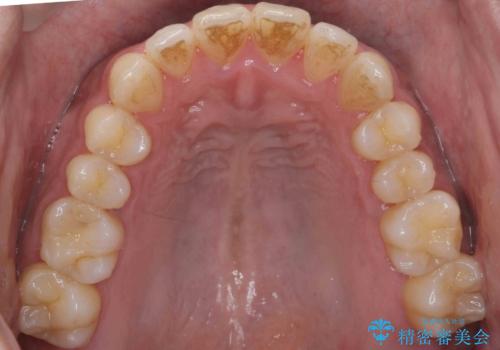

前歯が反対にかんでいる 部分ワイヤーとインビザラインの併用で短期治療

上はワイヤー部分矯正、下はインビザラインの部分矯正コースを行いました。

インビザラインだけでも治療は可能ではあると思いますが、ライトパッケージでは難しいと思います。

また、入れ替えを行う間左上の前歯だけで咬まなくてはならない状況になるため、マウスピース矯正単独で行うと時間がかかり、最悪神経が失活することもありますのでワイヤーがお勧めです。